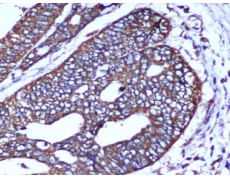

IHC positive control: |

Human colorectal carcinoma |

IHC Recommend dilution: |

25-50 |